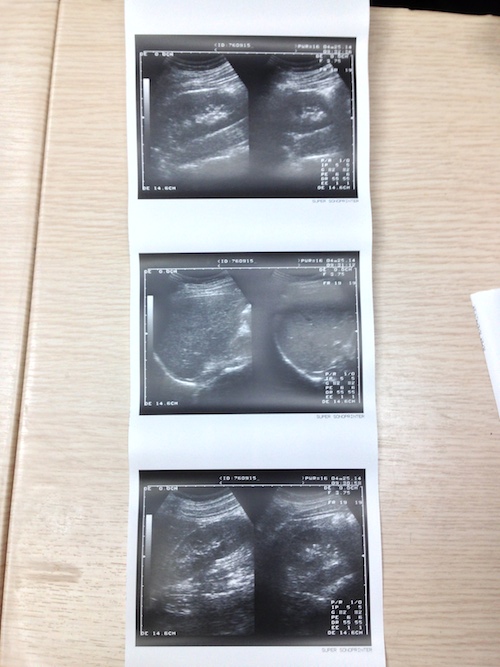

無論怎麼看⋯⋯都像孕婦的超音波檢查呀~我拿給朋友看,還以為我把女友⋯⋯

超音波給我的感覺是冰冰涼涼,所長拿著一根有滾輪的棒子,塗上特殊液體,然後在我肚子和脖子滾動,一旁的小螢幕有黑白畫面在動,就像電影裡和肥皂劇裡的情節那樣⋯⋯

所長跟我說看超音波幾個要點,

- 黑色的點

- 白色的點

- 陰影

是問題所在喲~幸運地我安然無恙:D~

拿這些影像去給親朋好友看,大多都會嚇一跳,甚至開玩笑說你要生了⋯⋯

由於沒有印給我的份,所以就用手機拍下來囉~